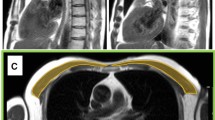

Measurement of pectoralis muscle index (PMI)

We measured the right pectoralis muscle area [cm2] at baseline and follow-up CT scans using CORESLICER, a validated web-based application for accurate assessment of muscular body composition [14]. Two readers (JW, CG) reviewed a single axial slice of chest CT above the aortic arch. Once the appropriate axial slice was found, readers used the software’s shading function to estimatearea (cm2) of the right pectoralis major and minor muscles. These raw pectoralis measurements were then indexed to the height square to calculate PMI (PMI: pectoralis muscle area [cm2]/body height2 [m2])).